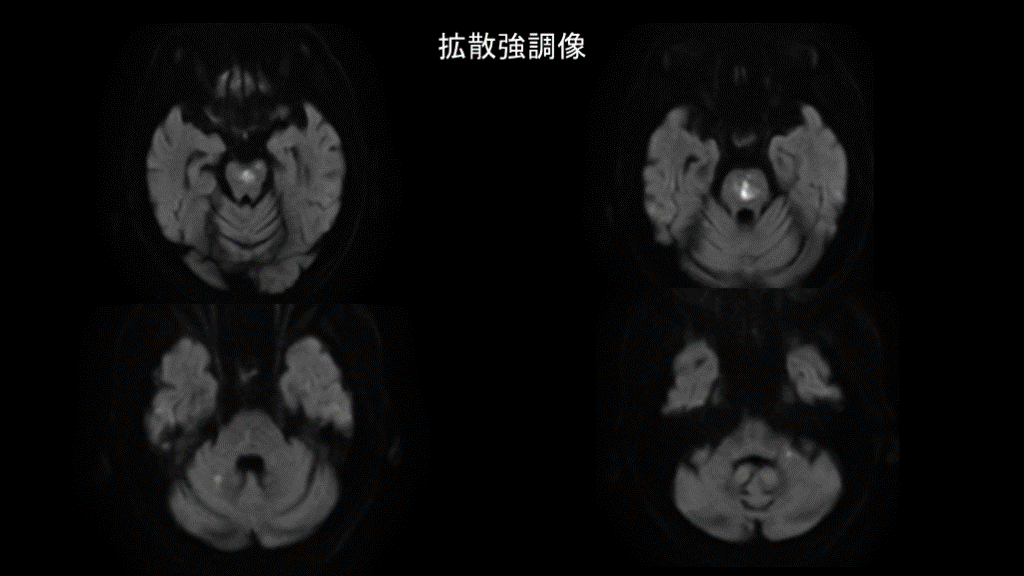

拡散強調像

#13.

症例1 アテローム血栓性脳梗塞(A to A embolism) ・梗塞巣が多発している ・梗塞範囲が小さい ・動脈硬化のリスクがある ・口径不整を多数認める 狭窄した椎骨動脈、脳底動脈で作られた 血栓が断片化し小梗塞が多発した

#15.